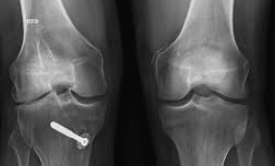

무릎 관절염으로 고생하는 환자들에게 줄기세포 치료는 인공관절 수술을 피할 수 있는 혁신적인 대안으로 주목받고 있습니다. 하지만 치료를 고려할 때 가장 먼저 궁금한 것은 바로 비용입니다. 무릎 줄기세포치료비용은 치료 방법과 병원에 따라 큰 차이를 보이며, 올바른 정보 없이는 과도한 비용을 지불할 위험이 있습니다.

가장 주목받는 골수줄기세포 주사치료의 무릎 줄기세포치료비용은 일반적으로 200만원에서 300만원 사이입니다. 이 치료법은 2024년 보건복지부의 신의료기술로 인정받아 안전성과 효과가 입증되었습니다.

골수줄기세포 치료의 세부 비용 구성을 살펴보면 재료대가 150만원에서 200만원, 시술비가 30만원에서 50만원 정도입니다. 환자의 골반에서 골수를 채취하여 원심분리기로 줄기세포를 농축한 후 무릎 관절에 주사하는 방식으로, 마취나 절개 없이 1시간 이내에 시술이 완료됩니다.